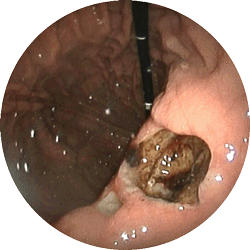

十二指腸潰瘍1

十二指腸潰瘍

お腹が張る,つかえる感じで

来院

内服薬にて1ヶ月で治癒